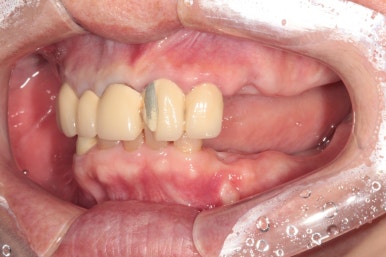

양옆으로 보았을 때도 아래 어금니는 모두 없어진 상태이고, 쓸수 있는 치아가 많지 않았어요.

왼쪽: 위턱, 아래쪽: 아래턱